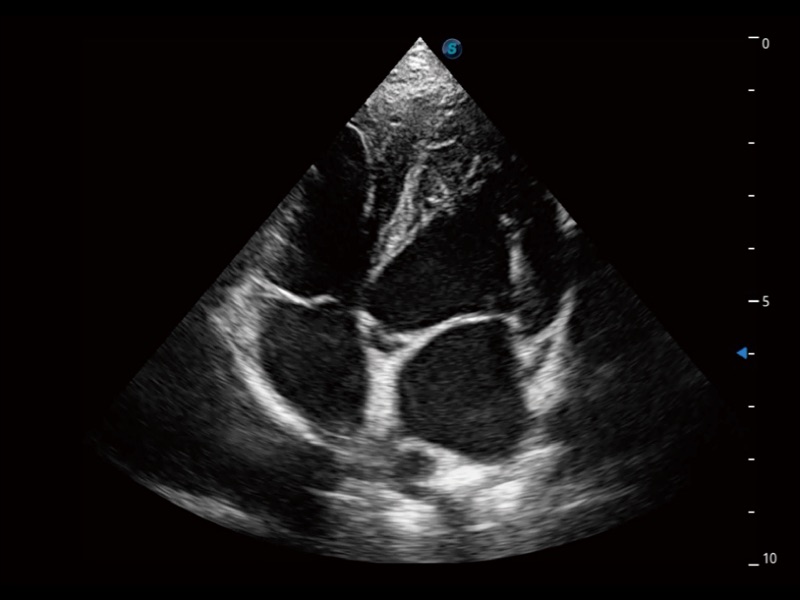

(犬)四腔心

(犬)四腔心MQA